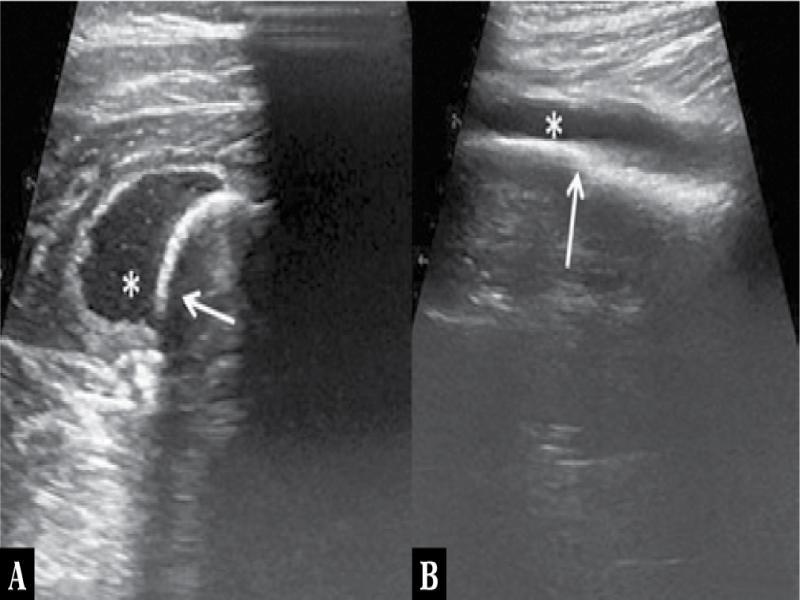

Fig. 1.

| Deep soft tissue fluid collection around the bone | 5 | 100 |

| Periosteal thickening or elevation with subperiosteal fluid collection | 4 | 80 |